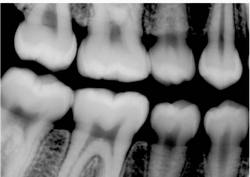

Finally, overall appearance of the image can be a very subjective assessment. Most dentists prefer image appearance and definition to be as much like conventional film as possible. The bitewing image in Figure 2 was taken with a CCD sensor and the bitewing image in Figure 3 was taken with a Soredex OpTime PSP sensor using a dry skull to maximize the definition of bone. Both images were made using the same kV, mA, and time, using the same enhancement features of the particular post-processing software utilized by the imaging system. From a purely subjective viewpoint, some dentists may prefer one image over the other depending on their personal likes and dislikes.